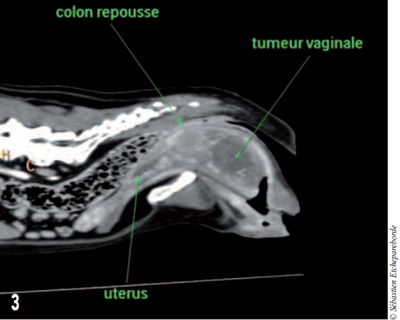

photo 3

Photo 3 – Coupe transversale de la masse où l’on aperçoit le colon comprimé dorsalement. La masse mesurait 10 cm de long.

Une sonde urinaire avait été mise en place préalablement pour repérer l’urètre au scanner. La masse mesurait 10 cm de long sur un diamètre d’environ 5 cm. Aucune des structures environnantes ne semblaient envahies par la masse.